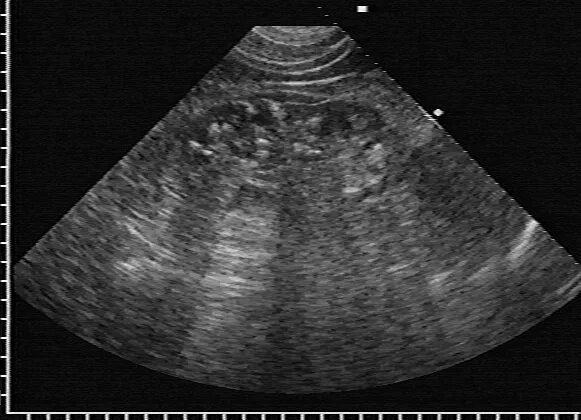

Кальцинат узи